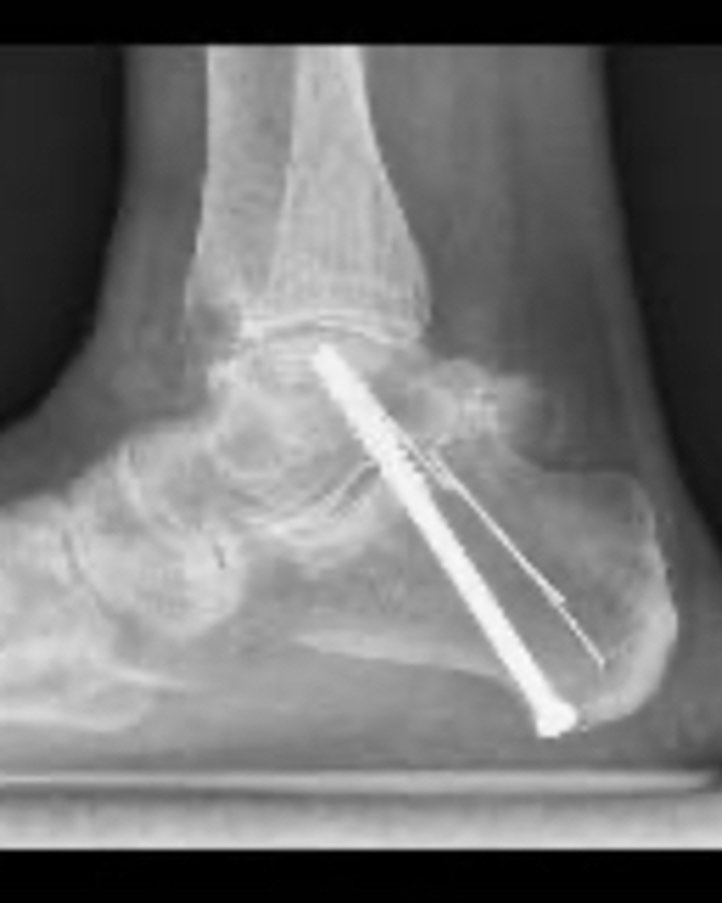

Este procedimiento quirúrgico consiste en sustituir la articulación dañada por una prótesis compuesta de metal y plástico, diseñada para restaurar la movilidad y aliviar el dolor.